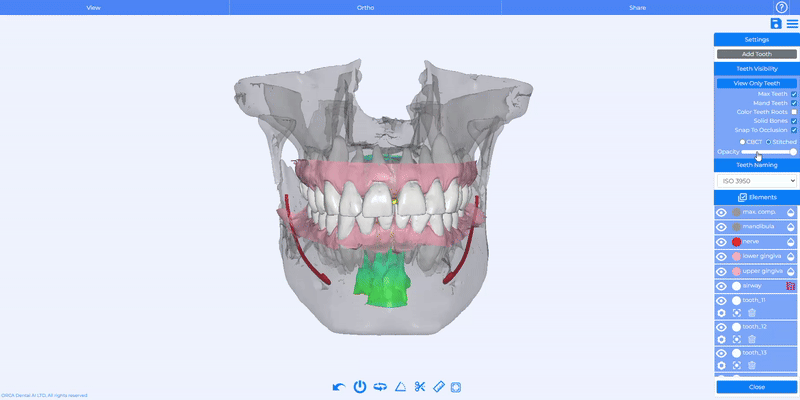

Enhanced Visibility Controls

You now have full control over visibility in the Tooth Panel: adjust the opacity of gingiva, bone, airway, and nerve with dedicated sliders.

How Does It Work?

Simply click the Drop icon to reveal per-element opacity controls and refine your view for more accurate treatment planning.

Solid Bones Toggle

We added a new Solid Bones checkbox to the Tooth Panel. It’s enabled by default and immediately switches bones to a solid rendering, making it easier to review anatomical structures and plan interventions.

You can easily activate or disable the “Solid bones” feature anytime with a quick toggle in the drop-down menu.

Snap to Occlusion

A new Snap to Occlusion feature is now available for stitched cases. When activated, it automatically aligns the models so the upper and lower teeth fit together correctly, making it easier for clinicians to assess bite relationships with greater accuracy.

You can easily activate or disable Snap to Occlusion anytime with a quick toggle in the drop-down menu.